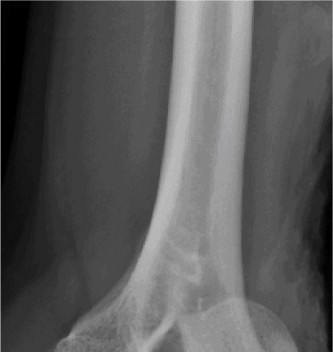

Physically examine a patient for classic posterolateral instability? Understand the potential treatment options? CASE 37 A 53-year-old, left-hand-dominant male presents to your office for evaluation regarding his elbow pain. He states that for the past 5 years he has had pain in his left elbow. It seems to be worsening over the past 6 months. He states he works as a mechanic and the pain is limiting the amount of time he can spend working. He takes anti-inflammatories with some relief. His images are shown (Figs. 2–97 and 2–98).

Figure 2–97

Figure 2–98

The correct answer is (A). Pain when carrying heavy objects with the elbow in extension is a classic presentation for patients with early disease. They also have

motion loss less than 15 degrees and respond well to conservative treatments. Patients with intermediate disease have moderate pain at the ends of motion, often have loss of extension >30 degrees and have ulnar nerve symptoms. Patients with end-stage OA have pain in the mid-arc of motion, have failed conservative treatment and have motion loss greater than 30 degrees.